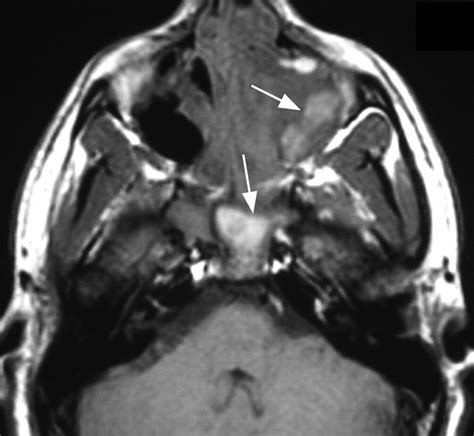

• Invasive Fungal Sinusitis: This is a serious medical emergency, typically seen in individuals with severely compromised immune systems (such as those with uncontrolled diabetes, transplant recipients, or cancer patients). It requires immediate and aggressive intervention.

• Nasal Endoscopy: A doctor uses a thin, flexible tube with a camera to look directly into the nasal passages and sinuses, checking for polyps or fungal debris.

• Computed Tomography (CT) Scan: This imaging provides a detailed view of the sinuses and can highlight calcifications or specific patterns characteristic of fungal growth.

Invasive cases require urgent surgical debridement (removal of infected tissue) alongside systemic (oral or intravenous) antifungal therapy. In all cases, treating any underlying issues, such as poor drainage or systemic immune compromise, is critical for long-term resolution.